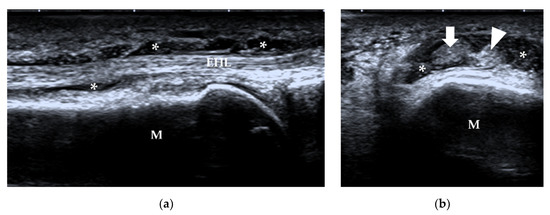

3.2.1. Tendons and Muscles of the Dorsal Foot

3.2.2. Tendons and Muscles of the Plantar Foot